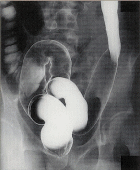

| ■診断の手順 慢性の粘血・血便などがあり本症が疑われるときには、放射性照射歴、抗生剤服用歴、海外渡航歴などを聴取するとともに、細菌学的・寄生虫学的検査を行って感染性腸炎を除外する。次に直腸あるいはS状結腸内視鏡検査を行って本症に特徴的な腸病変を確認する。その際、生検を併用する。これだけの検査で多くは診断が可能であるが、必要に応じて注腸X線検査や全大腸内視鏡検査などを行って、腸病変の性状や程度、罹患範囲などを検査し、同時に他の疾患を除外する。 棟方昭博:厚生省特定疾患難治性炎症性腸管障害調査研究班 平成9年度研究報告書 |

| ■診断基準 次のa)のほか、b)のうちの1項目、およびc)を満たし、下記の疾患が除外できれば、確診とする。 a)臨床症状:持続性または反復性の粘血・血便、あるいはその既往がある。 b)@内視鏡検査:i)粘膜はびまん性におかされ、血管透見像は消失し、粗像または細顆粒状を呈する。さらに、もろくて易出血性(接触出血)を伴い、粘血膿性の分泌物が付着しているか、ii)多発性のびらん、潰瘍、iii)偽ポリポーシスを認める。 A注腸X線検査:i)粗ぞうまたは細顆粒状の粘膜表面のびまん性変化、ii)多発性のびらん、潰瘍、iii)偽ポリポーシスを認める。その他、ハウストラの消失(鉛管像)や腸管の狭小・短縮が認められる。 c)生検組織学的検査:活動期では粘膜全層にびまん性炎症細胞浸潤、陰窩膿瘍、高度な杯細胞減少が認められる。緩解期では腺の配列異常(蛇行・分岐)、萎縮が残存する。 上記変化は通常直腸から連続性に口側にみられる。 b)c)の検査が不十分、あるいは施工できなくとも、切除手術または剖検により、肉眼的および組織学的に本症に特徴的な所見を認める場合は、下記の疾患が除外できれば、確診とする。 除外すべき疾患は、細菌性赤痢、アメーバ赤痢、サルモネラ腸炎、キャンピロバクタ腸炎、大腸結核などの感染性腸炎が主体で、その他にクローン病、放射線照射性大腸炎、薬剤性大腸炎、リンパ濾胞増殖症、虚血性大腸炎、腸型ベーチェットなどがある。 注1)まれに血便に気付いていない場合や、血便に気付いてすぐ来院する(病悩期間が短い)場合もあるので注意を要する。 注2)所見が軽度で診断が確実でないものは「疑診」として取り扱い、後日再燃時などに明確な所見が得られた時に本症と「確診」する。 棟方昭博:厚生省特定疾患難治性炎症性腸管障害調査研究班 平成9年度研究報告書